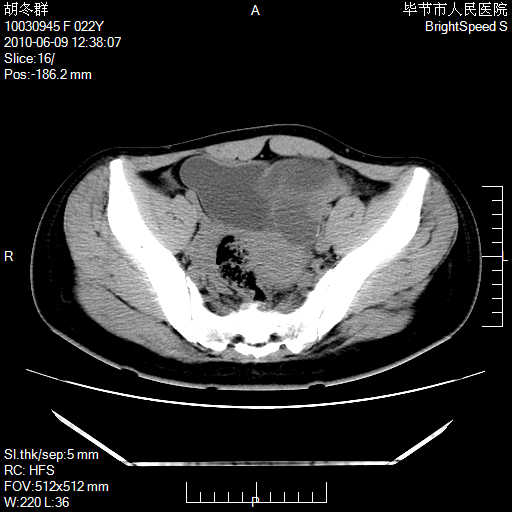

患者23岁,发现腹部包块3月。

左侧卵巢囊腺瘤或囊腺癌

盆腔内囊性占位性病变;考虑左侧卵巢囊腺瘤。

有分隔、壁薄,支持考虑左侧卵巢囊腺瘤。

左侧卵巢浆液性囊腺瘤。

支持考虑左侧卵巢囊腺瘤;宫腔积液。

有分隔、壁薄,支持考虑左侧卵巢囊腺瘤。排尿后,膀胱缩小,由于重力作用,肿块下移就到了膀胱位置,很好理解。